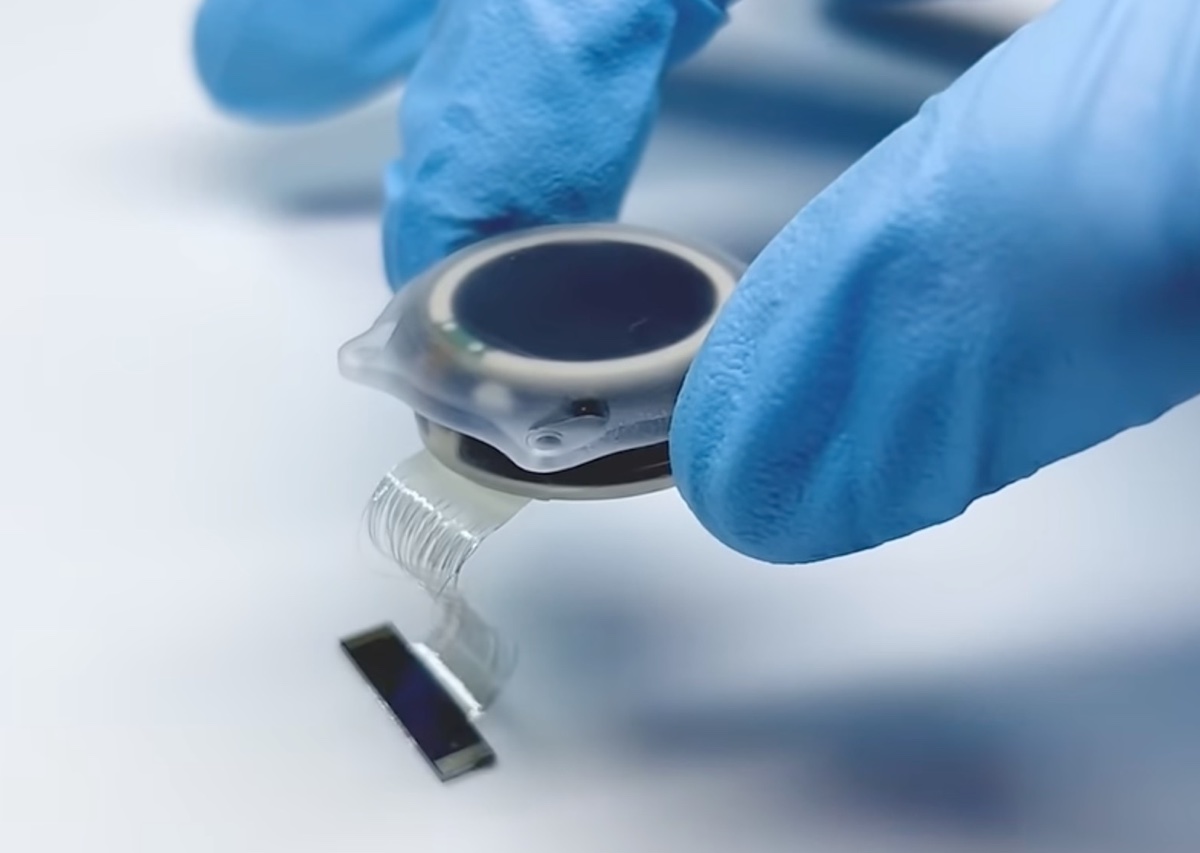

Secondo Neuralink, lo studio PRIME durerà circa sei anni, quindi le persone che desiderano partecipare ai test clinici dovranno essere pronte ad un impegno a lungo termine. Lo studio è diviso in due parti, con quello primario che durerà circa 18 mesi.

I pazienti dello studio PRIME di Neuralink dovranno anche essere pronti a partecipare a sessioni di ricerca per interfacce ceervello – computer BCI di un’ora almeno due volte a settimana.

Dopo i 18 mesi dello studio primario, i pazienti Neuralink entreranno nella fase di follow-up a lungo termine degli studi clinici umani, che si prevede durerà più di cinque anni. Tutte le notizie che parlano di Elon Musk sono disponibili nella sezione dedicata di macitynet, invece per gli articoli su Tesla si parte da qui.